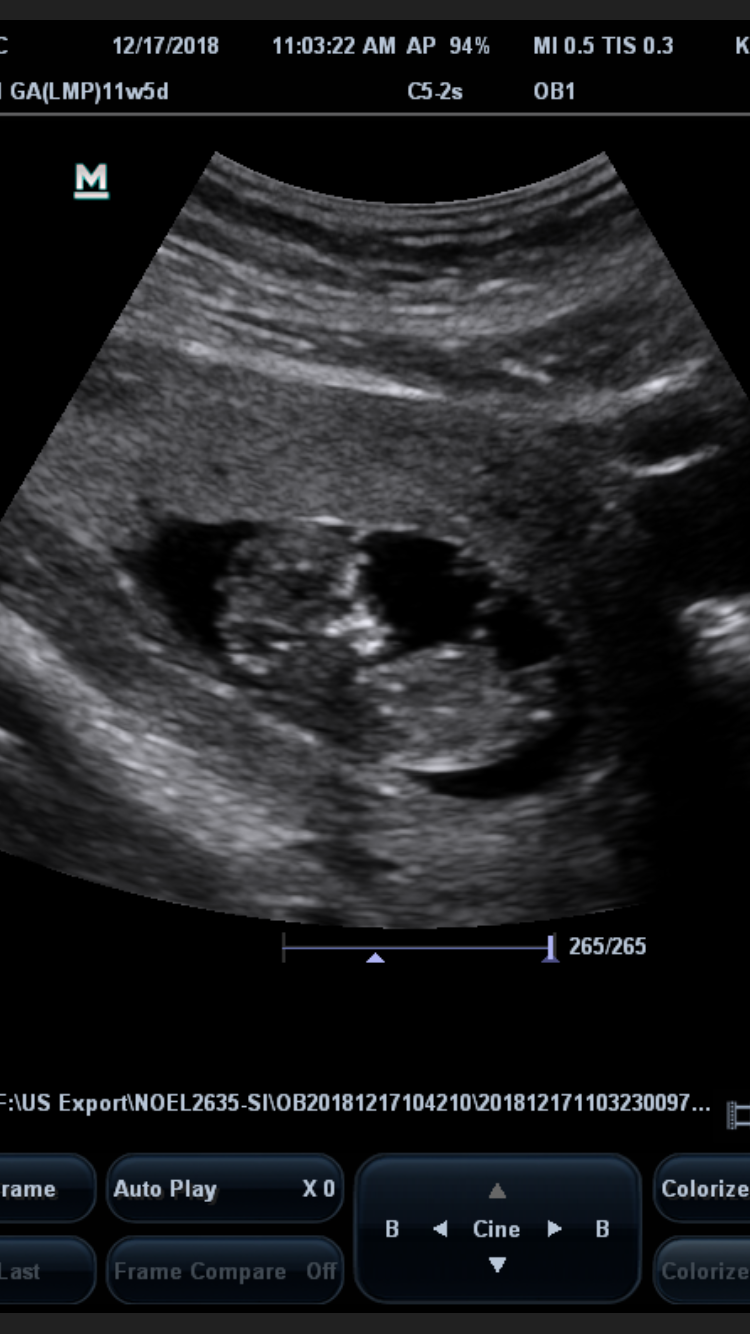

• our 3rd pregnancy but 2nd baby, baby measured at 11 weeks and day in this ultrasound,  which was done last Thursday the 20th. We get our 12 week nt ultrasound January 3rd. Even though it's my 2nd I'm still not showing, it's that normal?